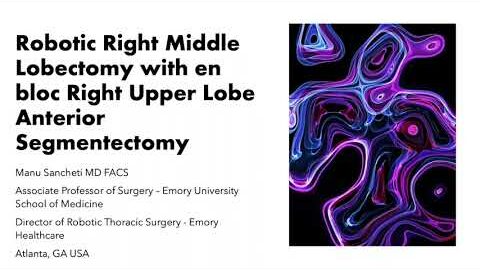

#229 Robotic Rt. Middle Lobectomy and Combined Right Upper Lobe Anterior Segmentectomy M. Sancheti

KS Awards, Robotics, Surgeon ';